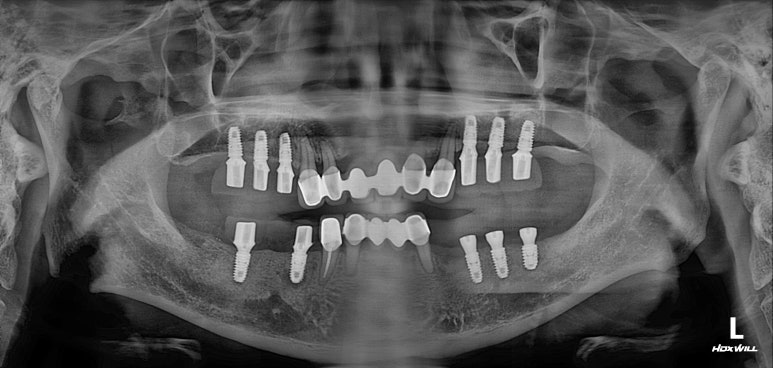

모든 최종 보철물을 연결하고 나서 치과용 파노라마 사진입니다.

정말 깔끔하게 제작된 것을 보시 수 있을겁니다.

'미적 기준'은 보편적인 측면이 있습니다. 뭔가 나란하고 비율이 대칭인 임플란트는, 잘 모르는 사람이 봐도 잘 되었구나~~ 라고 생각하게 만들어주죠 ^^

제가 가진 수술 경험을 비롯한 노하우와, 오스템 임플란트의 네비게이션 임플란트 시스템이 합작해낸 결과물!

1년이 지나서도 변함없지 잘 유지되고 있습니다.

수술을 잘 해내는 것도 중요하지만, 오래 쓰실 수 있게 해드리는게 더 중요하죠.

사실 임플란트 치료 완료 후 첫 1년을 별 문제 없이 지내셔야, 앞으로도 잘 사용하실 것을 기대할 수 있습니다.

그래서 저희 치과에서는 치료 완료 후 첫 6개월과 첫 1년 때 다시 한 번 전체 구강검진을 시행하고 있어요.

볼이나 혀가 씹히지는 않으신지, 양쪽 임플란트를 동시에 잘 쓰고 계신지..

그리고 임플란트 주변 잇몸에 염증은 없으신지, 나머지 자연치는 문제 없으신지 등등.

여러가지를 면밀히 살펴보고, 문제가 없으시면 이제 비로소 마음 놓고 6개월 정기검진으로 이행!

본 50대 남자 환자분은 1년이 지난 후에도 양쪽 모두 잘 씹으시면서 잘 사용하고 계셨고, 개선된 양치질과 치실 사용으로 다른 자연치아들의 잇몸건강까지도 깔끔하게 지켜내고 있는 모습이셨습니다!